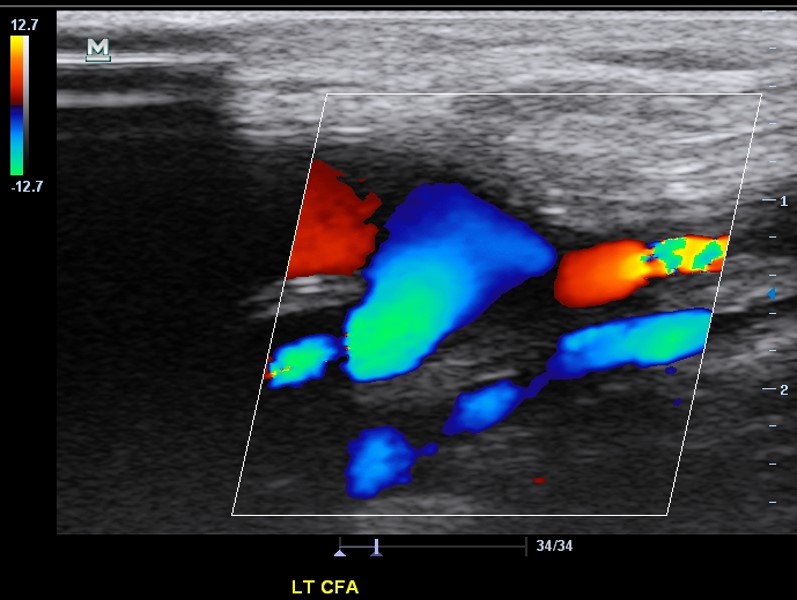

<p>The distal anastomosis of a fem-fem graft is demonstrated. Which of the following statements correctly describe the findings?</p>

The distal anastomosis of a fem-fem graft is demonstrated. Which of the following statements correctly describe the findings?

The native CFA demonstrates retrograde flow which is a normal finding.